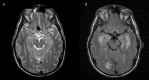

Transient amnestic syndromes are fascinating clinical entities and there are several subtypes. Transient global amnesia (TGA) is characterised by sudden onset of anterograde amnesia with repetitive questioning, lasting less than 24 hours. The pathophysiology of TGA involves the medial temporal lobes and hippocampi. Episodes of TGA are thought to involve venous congestion with Valsalva-like activities, vascular or migrainous mechanisms. In contrast, transient epileptic amnesia manifests as brief and frequent episodes of amnesia due to seizure activity in the temporal lobes. Transient memory disturbances can also be caused by transient ischaemic attack. We describe the first reported case of transient reversible amnesia directly attributable to acute demyelination. This case reminds us that multiple sclerosis relapses may present with acute cognitive impairment rather than the more classical physical symptoms. This is an important learning point in terms of appropriate management and eligibility for disease-modifying drugs.